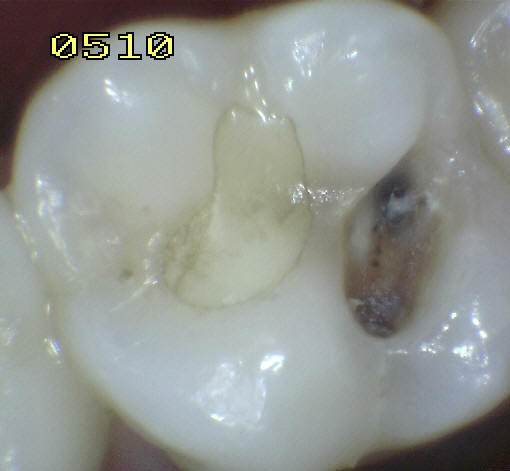

3 |

Restauración color

diente |

4 |

Amálgama |